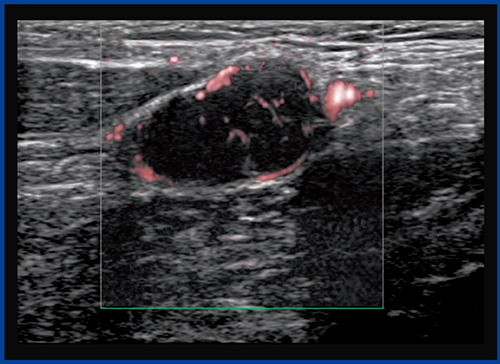

●症例3:神経鞘腫

症例3は,正中神経に発生した神経鞘腫で,カラードプラ(図8)では腫瘍の辺縁と一部の内部に動脈性の速い血流が認められた。内部にはあまり血流がないように思われるが,SMI(図9)では淡い血流が腫瘍内部に認められ,遅い血流があることがわかる。

従来のカラードプラやパワードプラ,ADFでは見えなかった血流がSMIで見えるようになることで,これまでは観察できなかった異常な血流の評価が可能になれば,腫瘍の鑑別や治療方針が変わることも十分考えられる。

なお,SMIはカラーモードに加え,より詳細な観察が可能なモノクロモードもあり,遅い血流の評価に有用である(図10)。

図9 症例3のSMI画像

腫瘍内部に遅い血流を認める。